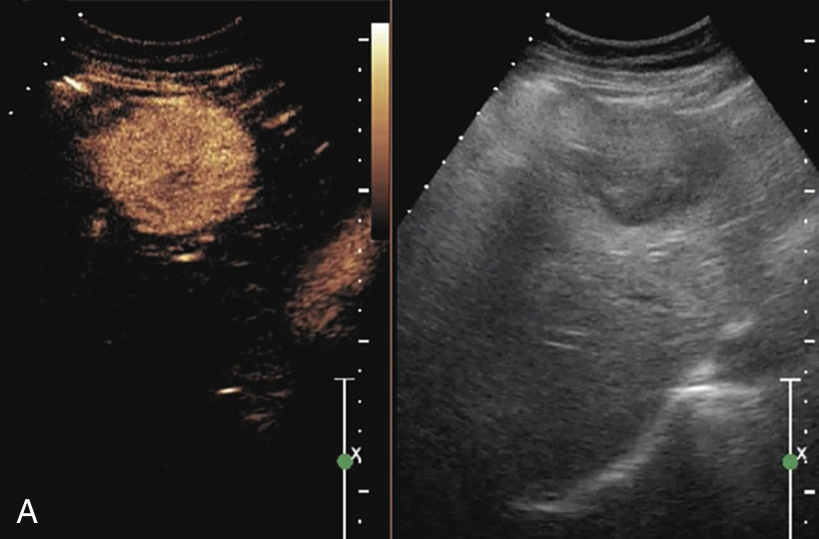

(3)回声特征:

病灶以实质性低回声为主,也可呈高回声或等回声,分布不均匀。肝内局部区域的胆管内径增宽,部分病例可不出现胆管扩张(图1-7-4)。

图1-7-4 肝内胆管细胞癌灰阶超声图像

肝右叶见较大混合回声,形态不规则,边界欠清